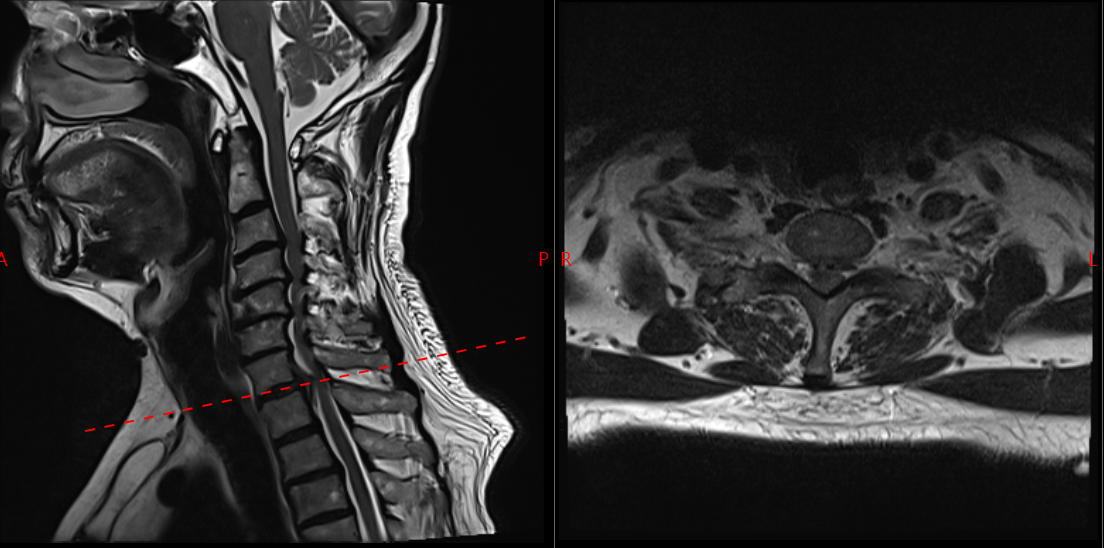

面对这一特殊情况,吴静晔主任没有急于下结论,而是为患者进行了细致全面的检查,最终精准诊断为脊髓型颈椎病。而进一步检查显示,患者存在 C3-T1 多节段狭窄,病情复杂且手术节段较多,这无疑给治疗带来了巨大挑战。

常规的治疗方案是颈后路 C3-T1 开门手术。虽能实现彻底减压,但手术损伤较大,对于 78 岁高龄的患者来说,是极大的考验。

为最大程度降低手术损伤,保障手术安全,吴静晔主任、王肖虎主任带领团队反复研讨,最终制定了更贴合患者情况的手术方案——C7-T2 节段全椎板切除减压、髓核摘除、椎弓根螺钉内固定术。

看似确定了治疗方向,真正的难题才刚刚开始。该手术区域解剖结构极其复杂,毗邻人体重要的神经、血管,堪称脊柱外科的「珠峰」。尤其是 C7-T2 椎弓根螺钉置入环节,传统手术极度依赖术中 C 臂透视,却因肩部遮挡,透视、定位极为困难,不仅手术视野受限、置钉难度陡增,螺钉还极易误入椎管,导致术中减压不充分,手术效果完全依赖主刀医生的丰富经验和精湛技术,是业内公认的「硬骨头」手术。